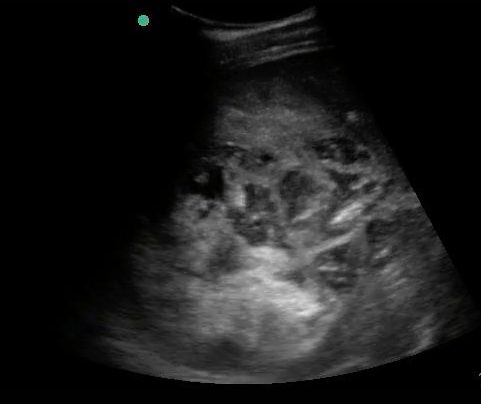

- Mechanical Risk Factors for Delivery

Figure 29. Transverse suprapubic view revealing the fetal cranium in the pelvis, consistent with a vertex presentation. Note the calipers measuring a bi-parietal diameter at 30 weeks and 6 days.